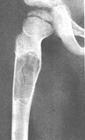

一X线:

X线平片位于长骨干骺端,呈圆形、卵圆形或柱形,沿长骨纵轴发展,表现为轻度膨胀性生长,局部骨皮质变薄,边缘光整,无骨膜增生。合并病理骨折时,骨碎片向囊内移位,称“碎片陷落征”,有助于鉴别。